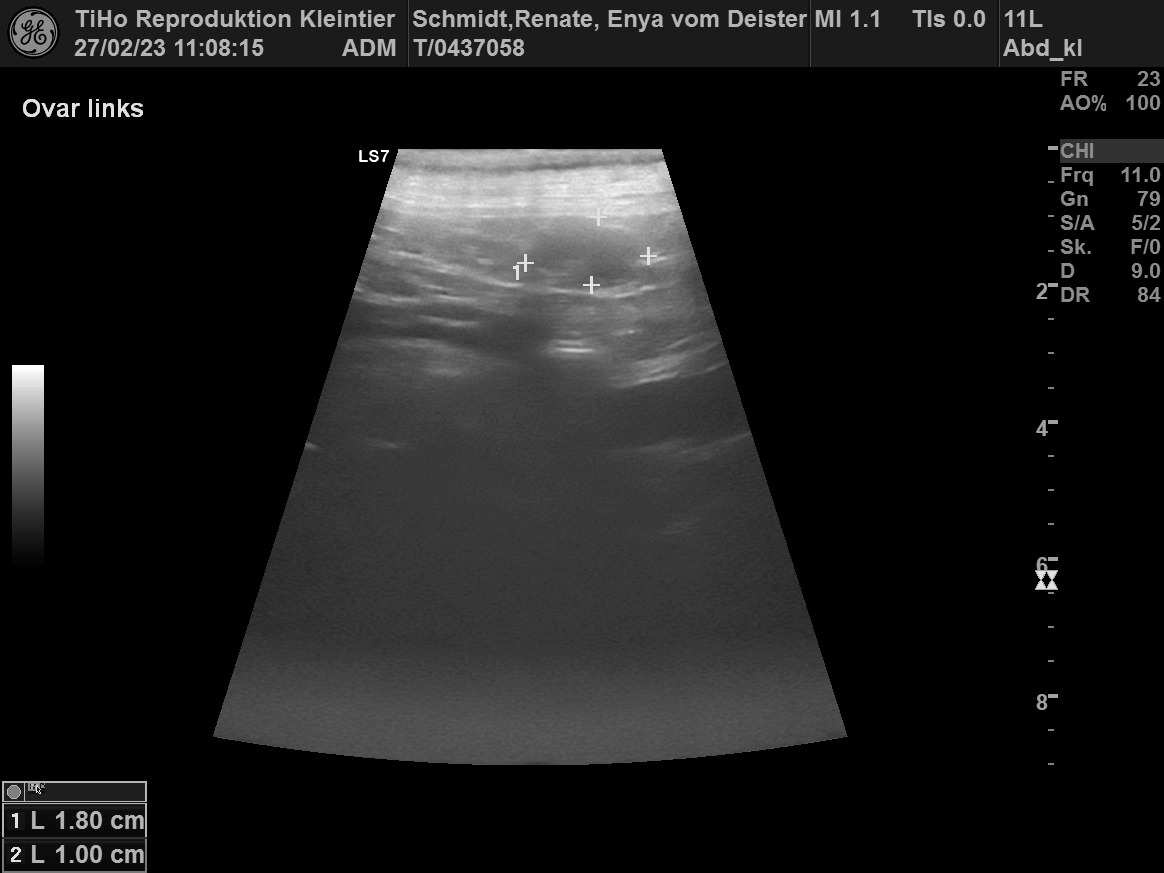

Beim Ultraschall am 25 Tag hat eine Frucht in etwa die Größe einer Weintraube.